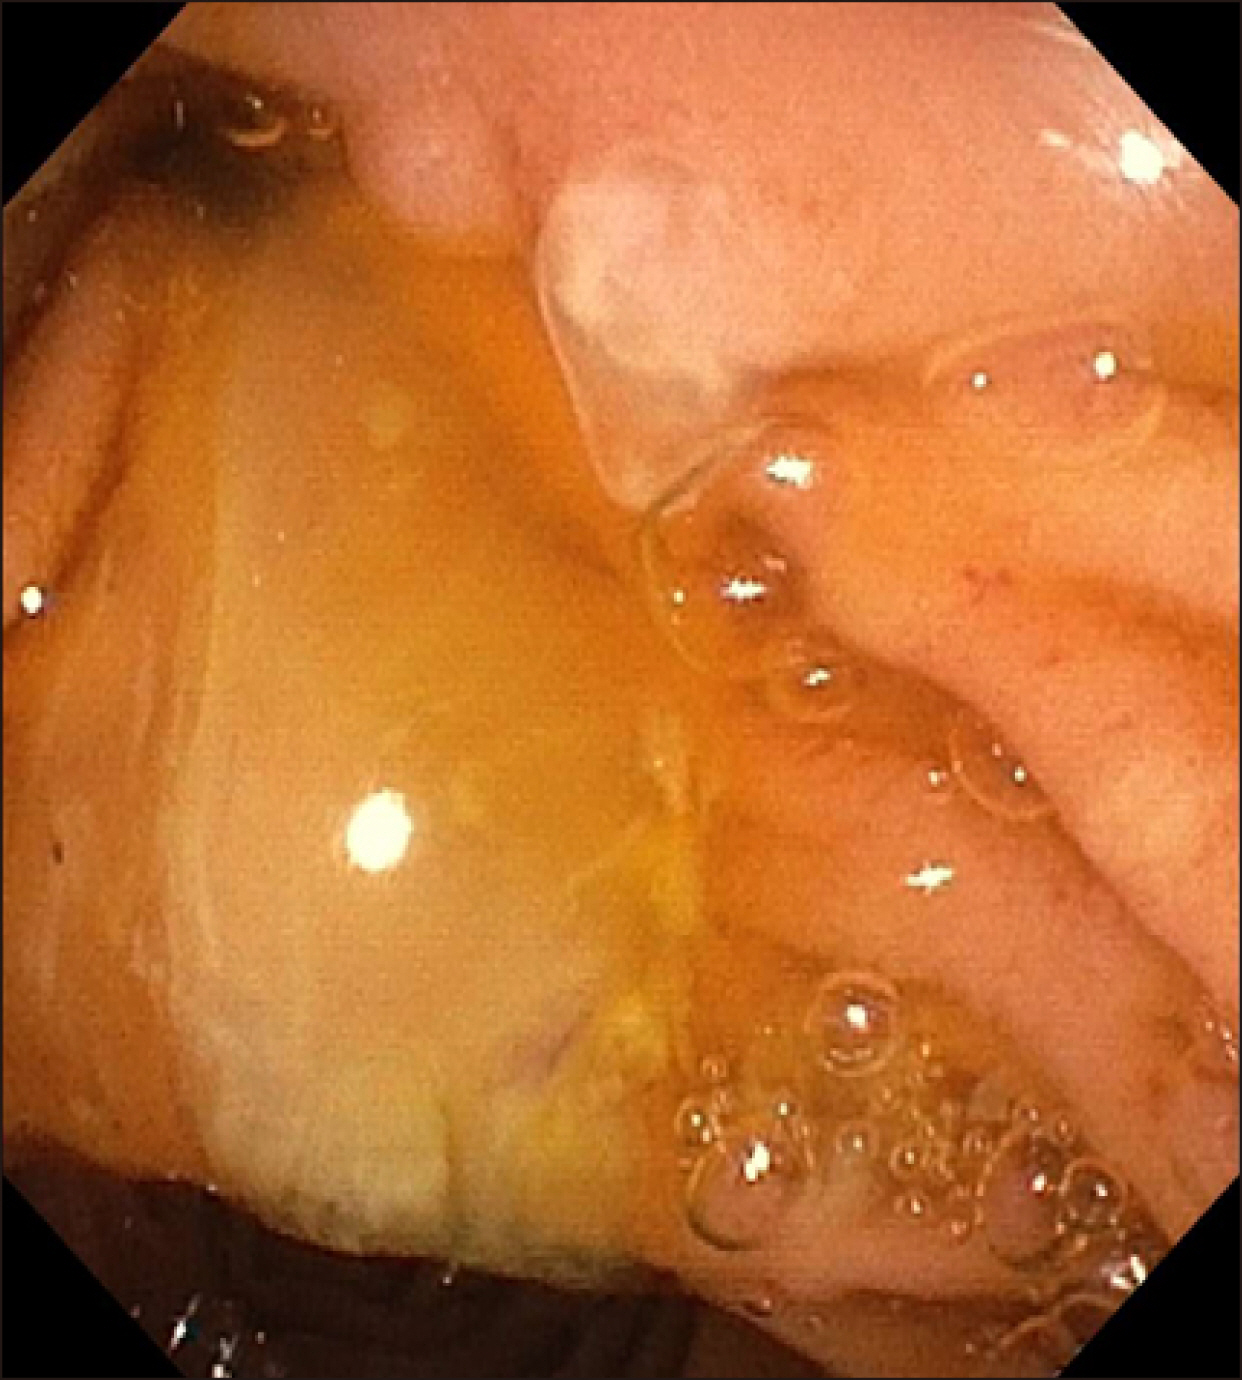

Recurrent pancreatitis in the setting of gallbladder agenesis,ansa pancreatica, Santorinicoele and eventual intraductal papillary mucinous neoplasia (IPMN)

- Gallbladder agenesis is a rare condition. Patients with gallbladder agenesis can present with biliary type symptoms and rarely pancreatitis. We present the case of a 35-year-old gentleman who was admitted and treated for recurrent pancreatitis on a background of gallbladder agenesis, ansa pancreatica and Santorinicoele. He has had several admissions with pancreatitis and has had multiple imaging modalities during these admissions which we delineate. We discuss this rare anatomical variant and describe the course and management of his illness leading up to his eventual diagnosis of intraductal papillary neoplasia (IPMN).